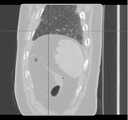

Fig. 8c is a schematic view of a sequence of CT images viewed from the coronal direction.

fig. 8a-8c are raw three-dimensional data of sequential CT images viewed from three directions, the transverse, sagittal and coronal planes, respectively. Fig. 9a to 9c are the second binarized images obtained after the method removes the bed plate area, respectively, and it can be seen from fig. 9a to 9c that none of the skin surface contours of the human body area is damaged. Fig. 10a to 10c are respectively third binarized images obtained after filling the cavity by the method, and it can be seen from fig. 10a to 10c that the third binarized images are completely overlapped with the original three-dimensional data of the sequence CT image, and the lung region with a low threshold value is effectively filled. As can be seen from FIGS. 11a-11d, after another serial CT image is reconstructed by the method, the three-dimensional model of the skin can be fused with the third binary image and the serial CT image. And finally mapping the obtained three-dimensional model of the skin back to a 2D mode, and comparing the coincidence degree of the skin boundary in the three-dimensional model of the skin and the binary image to obtain figures 12a-12 c. In addition, the three-dimensional models of the skin of other parts of the human body obtained by the method are shown in figures 13a-13 c.